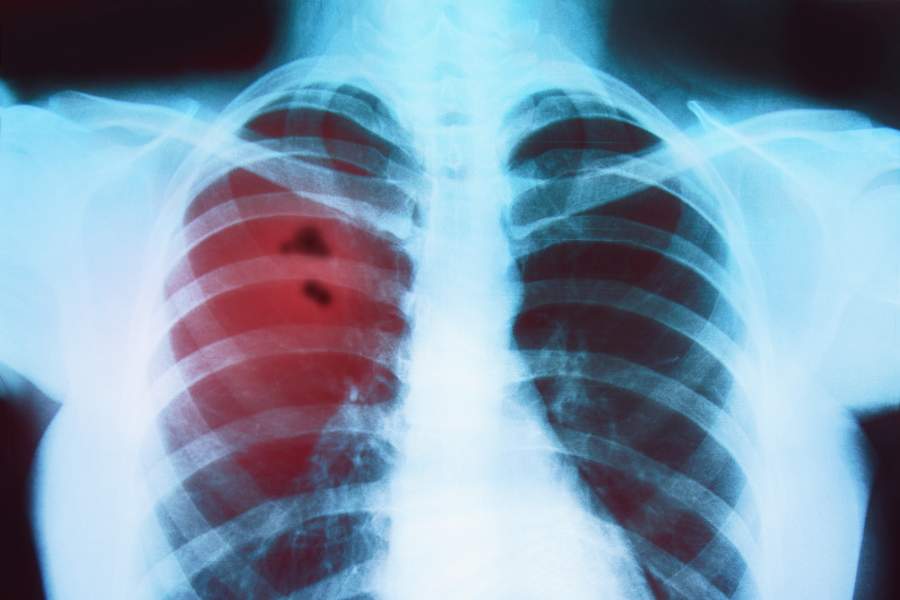

Bronchitis

Bronchitis is an inflammation of the mucous membranes of the bronchi (the larger and medium-sized airways that carry airflow from the trachea into the more distal parts of the lung parenchyma). Bronchitis can be divided into: